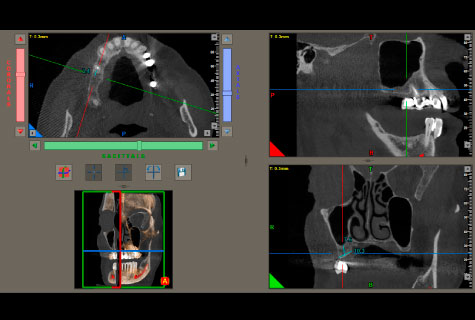

- Único que incluye programa para colocación de implantes virtual.

- Marcación del dentario inferior para un mejor diagnóstico.

Tomografía Cone Beam

- Tomografía de maxilares

- Tomografía Macizo Facial

- Tomografía senos paranasales